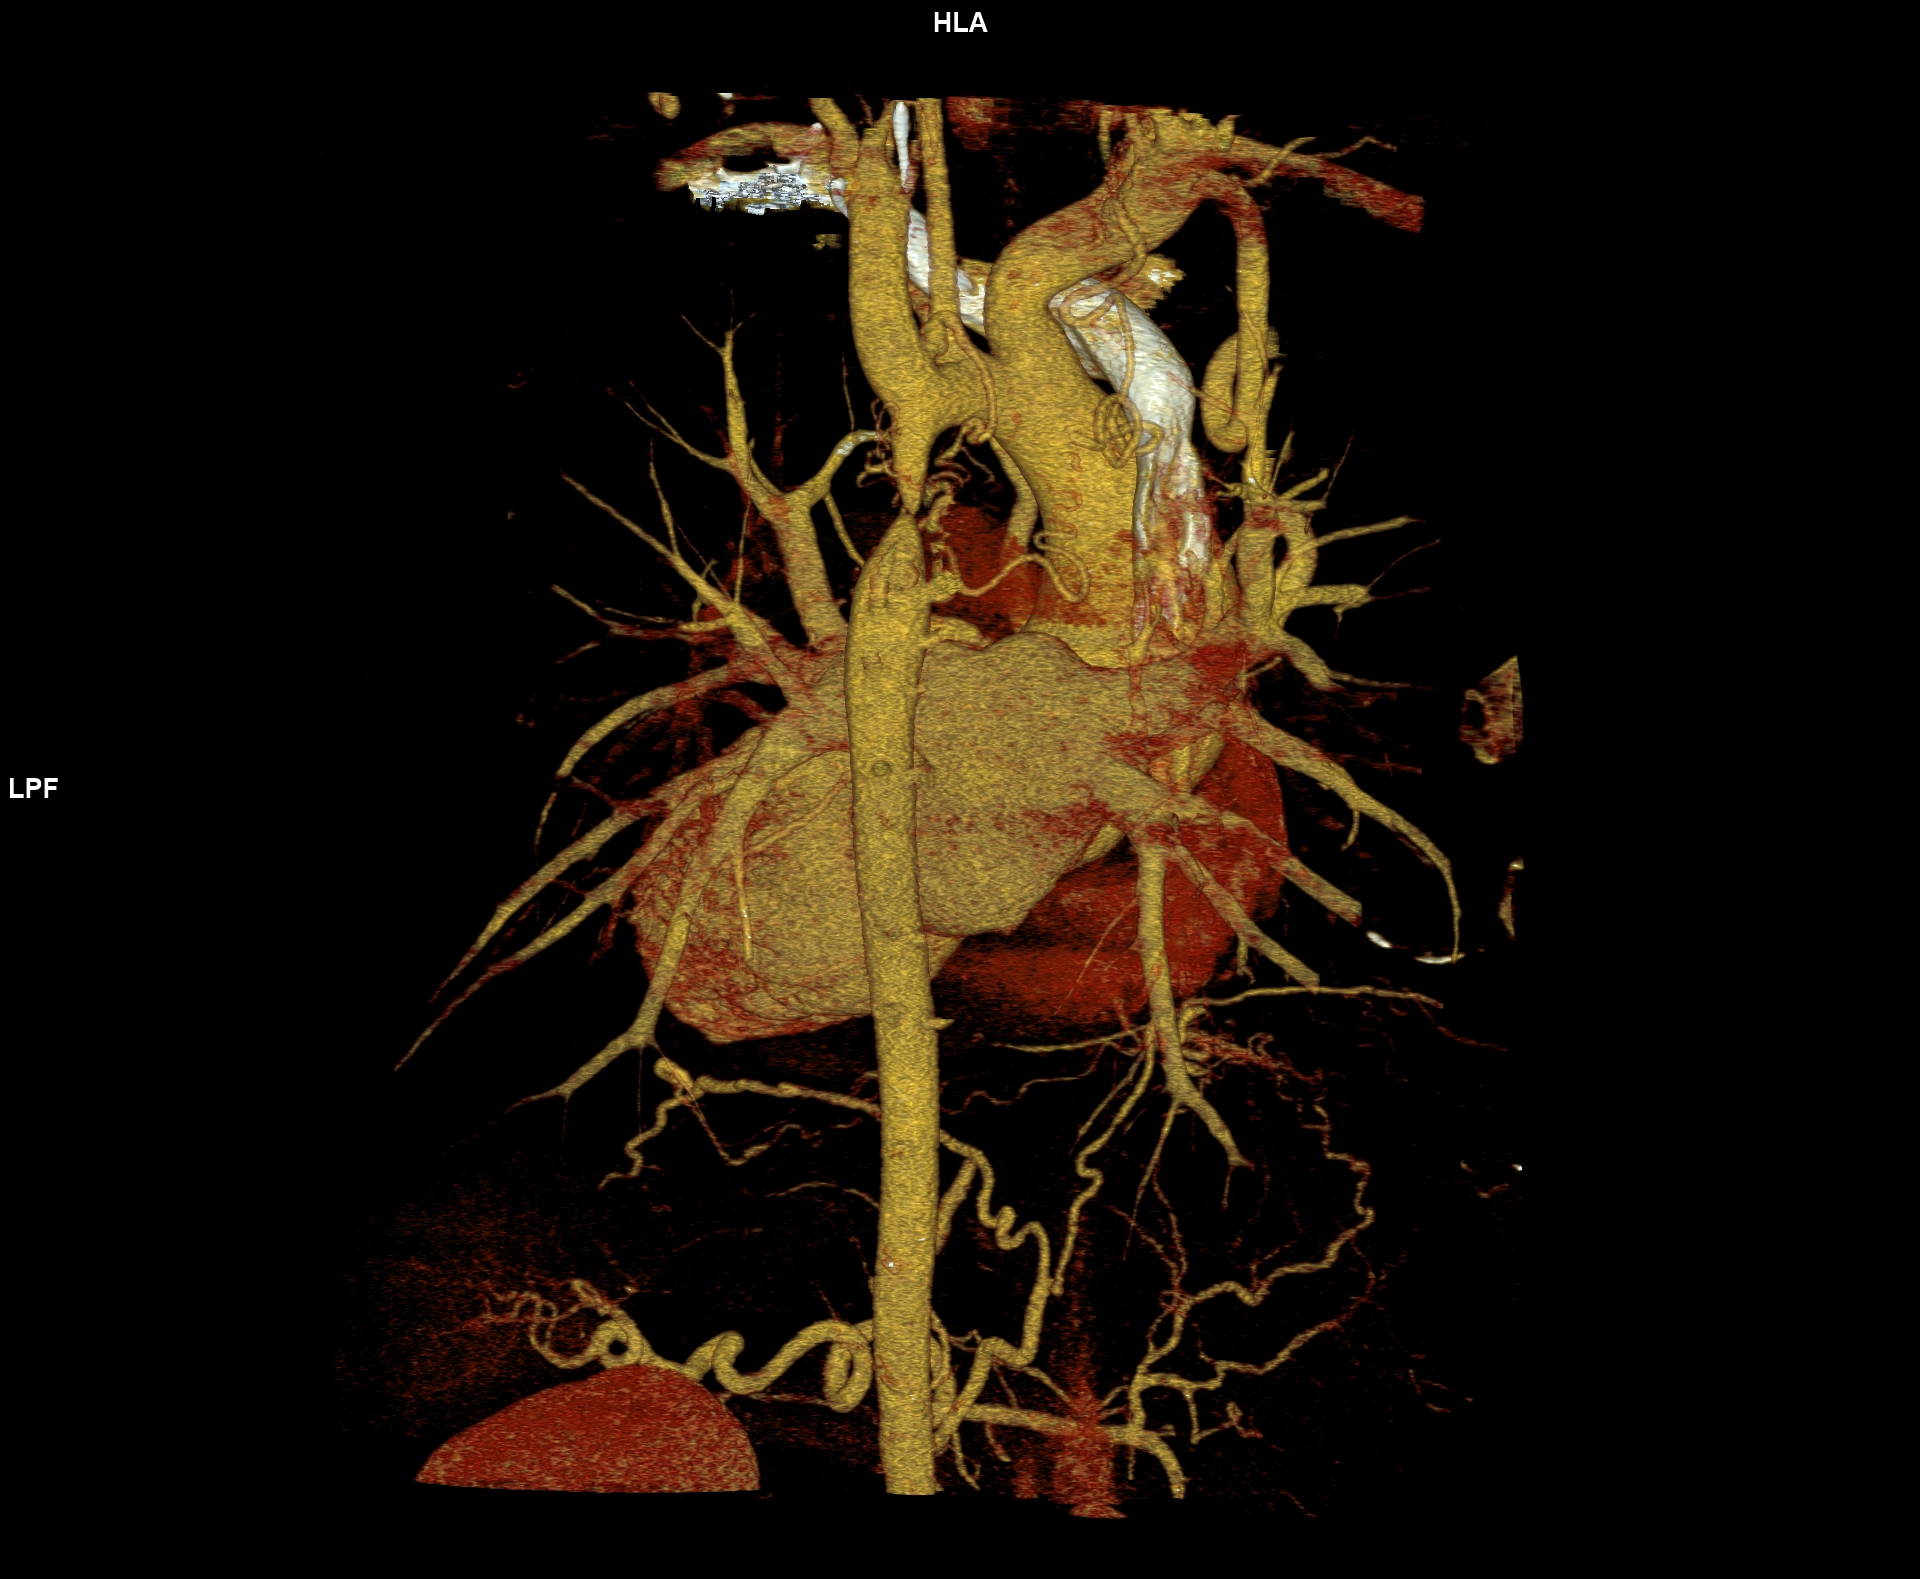

Figurile 6-10: reconstrucții volumice (VRT) din achiziție angioCT aorta toracică

Discuţie caz nr 109: Pacient cu suspiciune de coarctaţie de aortă – are indicație de angioCT aortă toracică; medicul radiolog la acești pacienți este indicat să efectueze investigația cu sincronizare ECG deoarece coarctaţia de aortă poate fi asociată și cu bicuspidie de valvă aortică, mai ales că la acest pacient ecografia cardiacă descria creștere de calibru a aortei ascendențe. Pe reconstrucția cine în planul valvei aortice din achiziția cardioCT cu sincronizare ECG se remarcă o valvă aortică morfologic tricuspidă, funcțional bicuspidă ce asociază ectazie de aortă ascendentă și coarctaţie de aortă descendentă cvasicompletă cu dezvoltare de circulație colaterală intercostală și mamară internă.